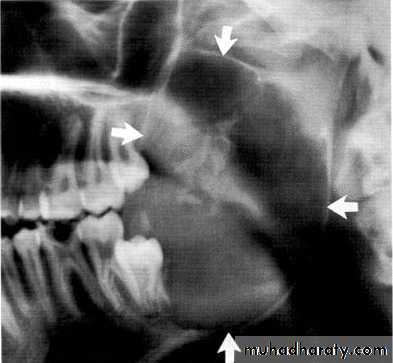

Maxillary lesions can extend into the paranasal sinuses, orbit or base of the skull.

The maxillary left canine and premolar have been displaced superiorly by the tumor.

The canine and lateral incisor have been displaced by the lesion.Soap bubble-like radiolucencies